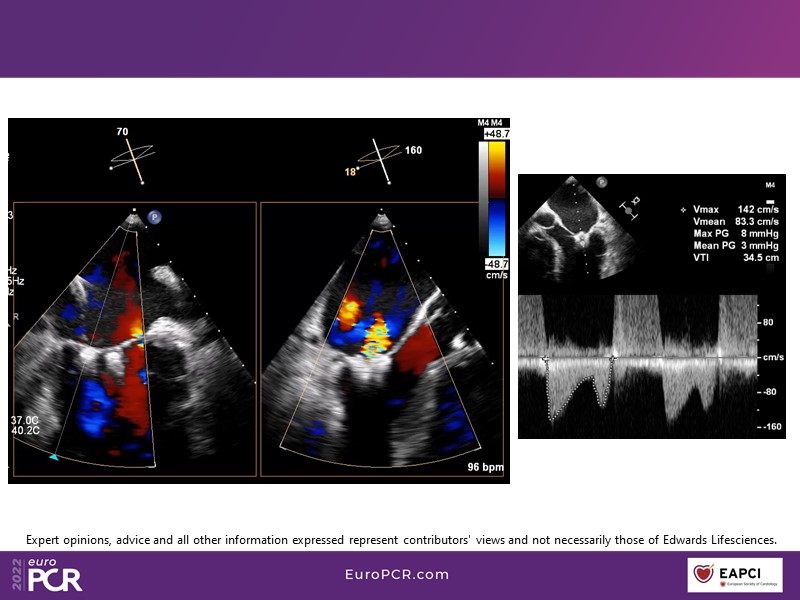

With study outcomes and clinical cases, this EuroPCR 2022 session will enable you to discuss the anatomical considerations that define suitable candidates for treatment of mitral regurgitation with the PASCAL platform and highlight key differentiators and tips and tricks for its use.

- To discuss which anatomical considerations define suitable candidates for the treatment of mitral regurgitation with the PASCAL platform

- To attend case-based discussions that will highlight key differentiators and tips and tricks when using the PASCAL platform to treat mitral regurgitation